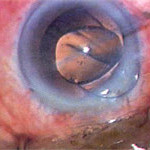

CATARACTOUS LENS BEING BROKEN BY PHACO NEEDLE THROUGH

1 MM to 2.8 MM IN INCISION

FINAL CLEANUP